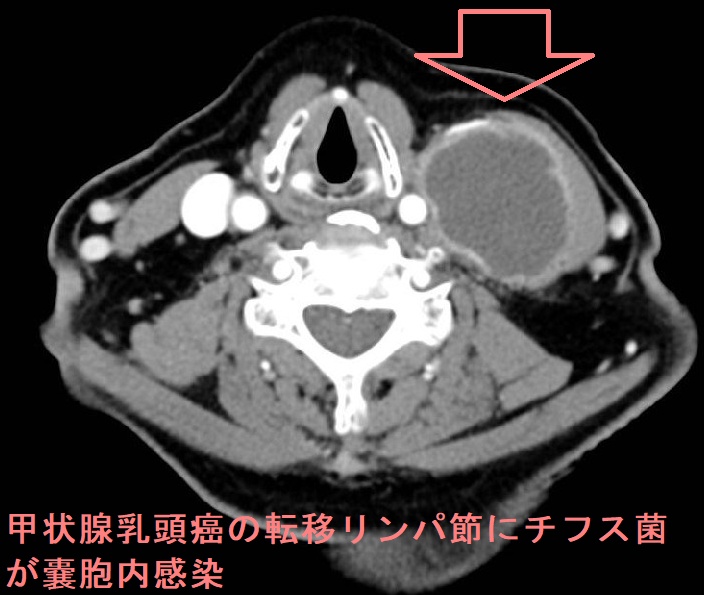

甲状腺乳頭癌の転移リンパ節にチフス菌(Salmonella Typhi)が感染(嚢胞内感染)し、サルモネラ誘発性頸部膿瘍を発生した報告があります。[Case Rep Med. 2017;2017:5670429.]